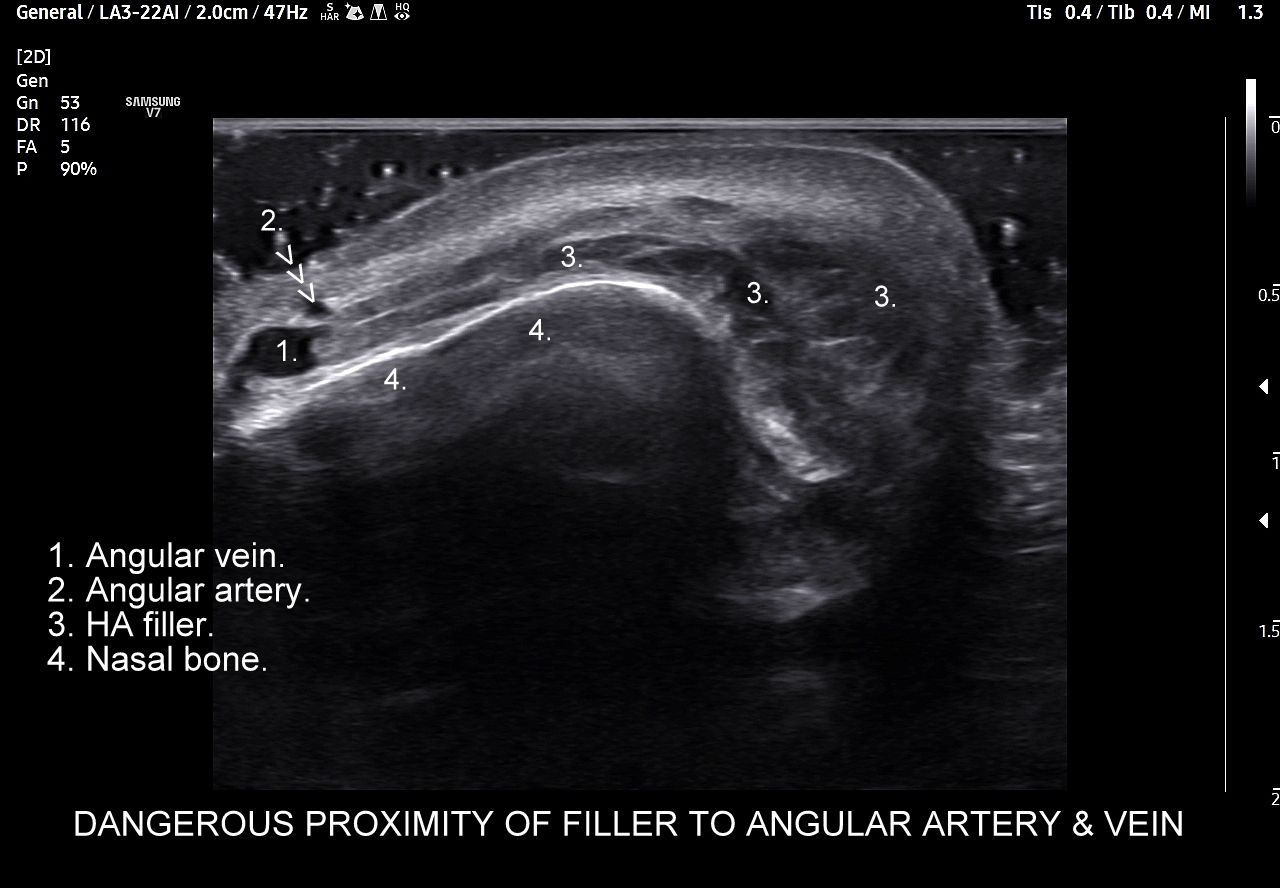

Należy również podkreślić, iż ze względu na gęste upakowanie naczyń, bezpośrednią bliskość anastomoz i często obecność szerokiej, acz niewidocznej żyły kątowej szczególnie niebezpiecznym w aspekcie deponowania wypełniaczy czy wystąpienia lokalnych stanów zapalnych jest obszar u nasady nosa, przy wewnętrznych kącikach oczu i na gładzinie (łac. glabella). Na załączonych do artykułu skanach zobaczyć można czym jest trójkąt śmierci na twarzy i na tej podstawie uzmysłowić sobie, dlaczego tak właśnie się nazywa. Proszę zwrócić uwagę na przykład ekstremalnej bliskości nieodpowiedzialnie zdeponowanego u podstawy nosa wypełniacza, tu kwasu hialuronowego, w stosunku do struktur naczyniowych.